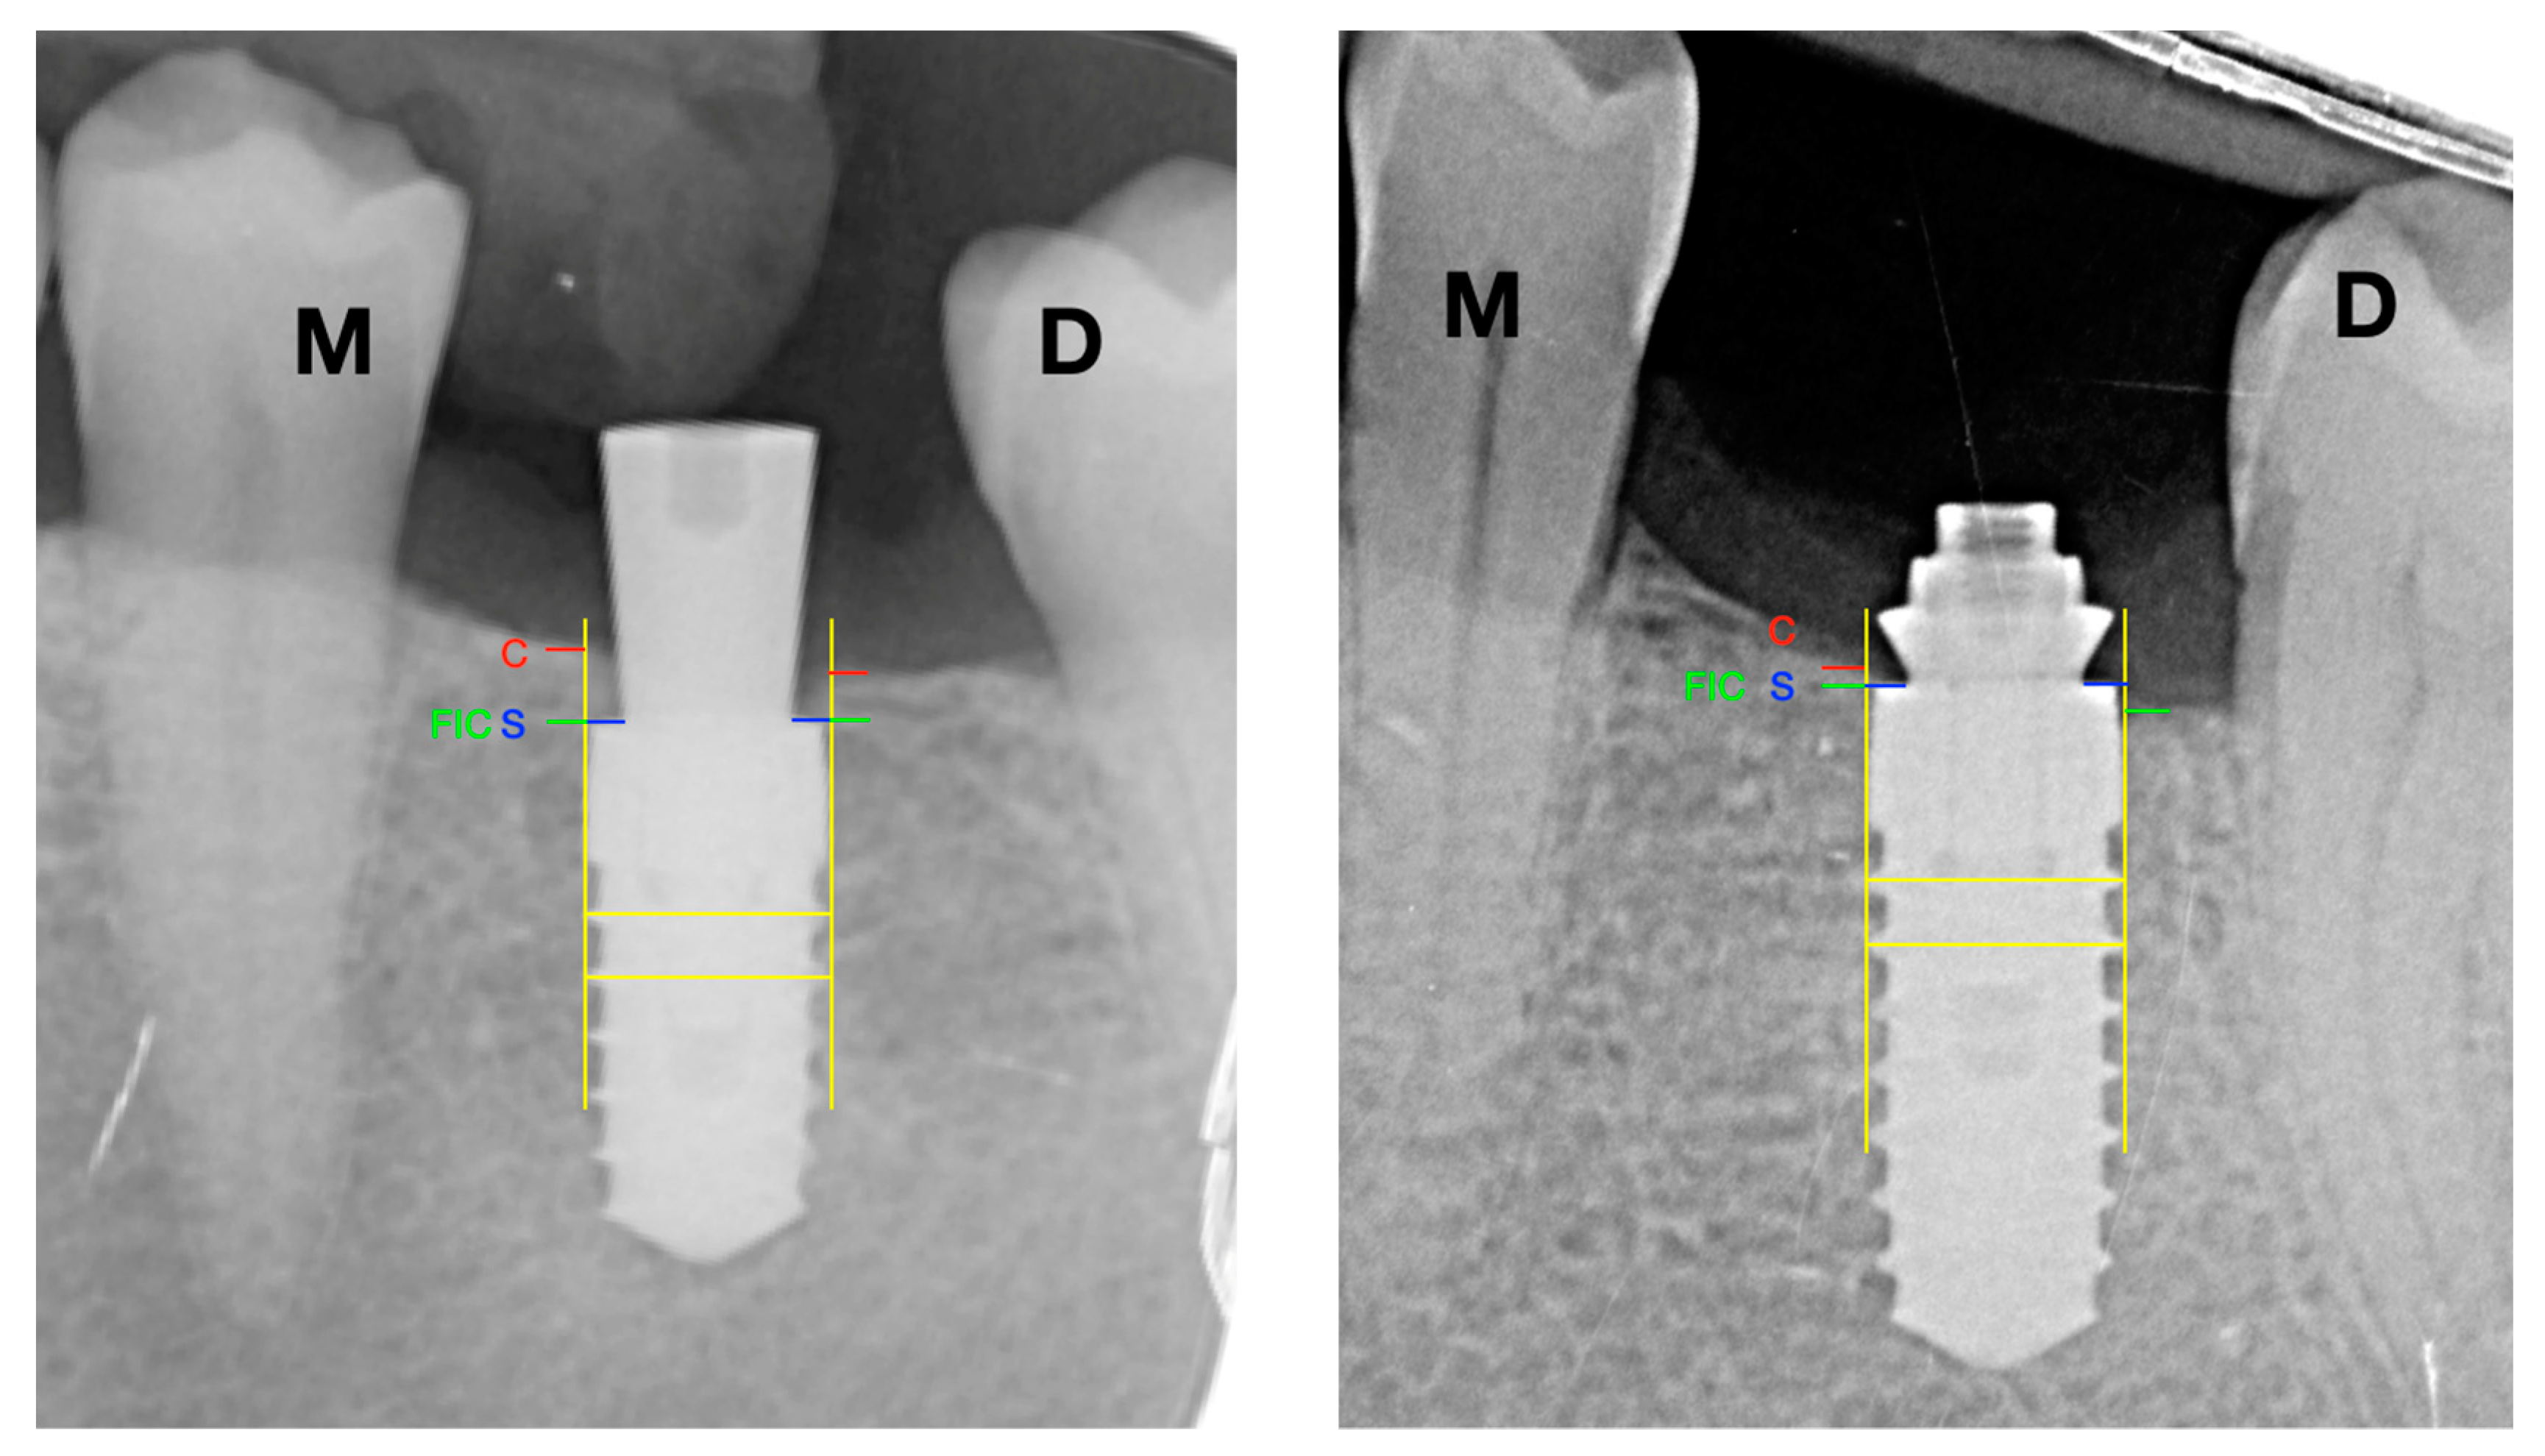

Consequently, all radiographs were calibrated by assessing their possible distortion, using the distance between the threads of the implant body as a known value. All implants were evaluated by drawing vertical lines parallel to the long axis of the implant, taking the implant platform (S) as the starting point, then the mesial and distal crestal bone level of each implant was recorded. Besides cases of presenting bone tissue on the platform, the measurement was from platform to bone crest (C). In addition, in cases where the bone crest (C) was apical to the implant platform, the distance between the platform (S) and the first bone-implant contact (FIC) was measured—see Figure 3.

Negative values (−) were established in case the implant platform was subcrestal and positive values (+) if it was coronal to the bone crest.

For the statistical analysis, the value was obtained using a mean between the mesial and distal values of radiographic bone loss.

Two operators, previously calibrated (BRC and GTG), marked the turns, implant platform (S), bone crest (C), and first bone-implant contact (FIC) and measured the distances between turns, SC, and S-FIC using the ImageJ software (National Institutes of Health, Madison, MD, USA).

Figure 3. Radiographic analysis. S: implant shoulder; C: bone crest; FIC: first bone to implant contact; M: mesial; D: distal; SC distance: marginal bone level at the crest; S-FIC distance: marginal bone level at the implant.